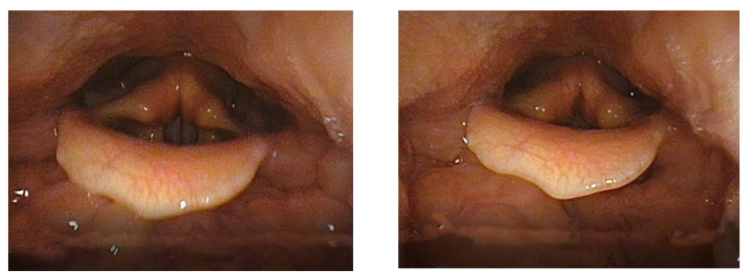

According to Stark, a correct Garcia Coup de la Glotte starts with closing the arytenoid cartilages, as shown in Image 4. This results in only the membranous glottis vibrating when the phonation starts. This shortens the glottis during the phonation minimizing the air flow and creating the tone quality that Garcia required. This, according to Stark, is the difference between the Coup de la Glotte and the simultaneous onset, which may be set with full glottal length.[33] Stark claims that when the arytenoid cartilages are not closed tightly enough, the full glottal length would vibrate and create a veiled quality of tone that Garcia wished to avoid.

Image 5a & 5b

Images 5a and 5b are Garcia’s pictures. They are not exactly the same as Stark’s. Image 3a shows the opened glottis and Image 3b shows the closed glottis without explaining which part is vibrating during the phonation. However, in 1855, Garcia indicated an explanation similar to Stark’s: “This deep contact, which continues even after the apophyses no longer partake in the vibrations, gives a deep tension to the membranes, increases the depth of their contact, and, as a necessary consequence, augments the resistance they present to the air.”[34] To my understanding, Garcia explains that the arytenoid cartilages are not vibrating during the phonation, although he does not say here if this is unique to the case of Coup de la Glotte. In 1847, before his invention of the laryngoscope, Garcia explains that the glottis lips may still vibrate “either when the posterior extremities are put into contact (by bringing together of the internal processes of the arytenoids), or when these extremities remain separated. In the first case, the sounds are emitted with all the brilliance possible; in the second, the voice takes a dull character.”[35]

The experimental component of this research suggests that the technique of Coup de la Glotte may function better when used in conjunction with the technique of Voix Blanche. The glottis filming indicates that Coup de la Glotte tends to constrict and narrow the vocal tube. The pharynx is pressed inwards and the larynx tends to place itself in a slightly higher position.

Image 11 & 12: The filming was made by Inselspital Bern

Image 11 illustrates the onset of F5 without Coup de la Glotte. Image 12 illustrates the exact moment of onset of F5 with Coup de la Glotte. When the onset is executed whith Coup de la Glotte the pharynx muscles presses inwards, narrowing the vocal tube. The constriction even seems to push the larynx slightly upwards. It may be possible to train the larynx to stay fixed in low position when executing Coup de la Glotte, although this experiment suggests that it naturally rises. This indicates that the technique of Coup de la Glotte best suits the high larynx position, not a fixed lowered larynx which Stark and Austin claim to be Garcia’s intention.[75] The Coup de la Glotte causes a slim, narrow vocal tube. The wideness of the vocal tube affects the formants and, consequently, the timbre. Garcia claimed that the Coup de la Glotte gives stability to the tone and phrase. This narrow timbre, as illustrated in the middle of image10, was probably his vocal ideal.